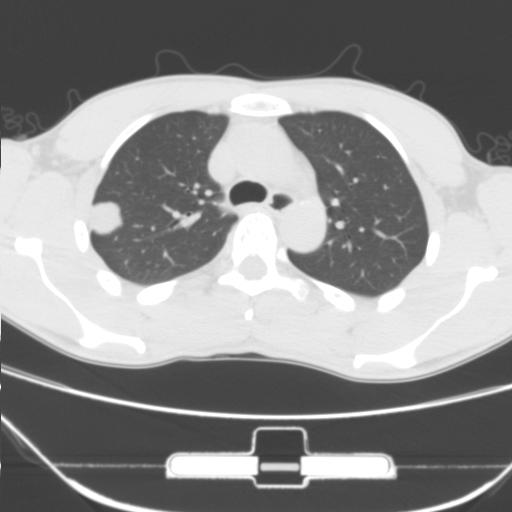

标题: CT25483:肺部病变 请指教

车祸伤者

右肺上叶后段近胸膜下结节样异常密度灶,似见分页及毛刺,考虑右肺上叶周围型肺ca,建议穿刺病理检查

缺乏病史,症状体征,但这个孤立结节具备了几乎所有的恶性征象:分叶,毛刺,空泡征,胸膜凹陷征,血管集束。